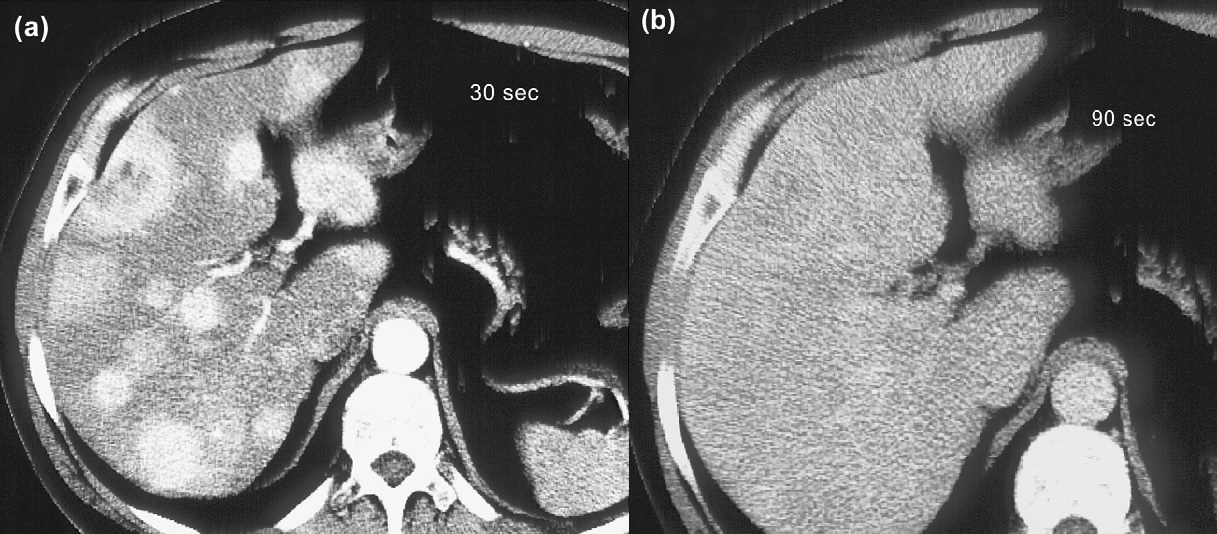

Exames de imagem são fundamentais para localizar o tumor primário, identificar sítios de doença metastática, investigar a expressão de receptores de somatostatina e avaliar a resposta ao tratamento. Tomografias (TC) e ressonâncias (RNM) são os métodos anatômicos mais empregados, mas cuidados técnicos são essenciais para otimizar a sensibilidade dos exames. A RNM é ligeiramente superior à TC, principalmente na avaliação do fígado e do pâncreas. Metástases hepáticas de TNE podem ser de difícil identificação à TC, uma vez que são comumente isodensas em relação ao fígado nas imagens de fase venosa portal (figura 1). Por esse motivo, a realização de exame trifásico é recomendada (LEUNG, 2013). A avaliação de resposta por RECIST tem limitações em TNE, assim como em outras neoplasias em que agentes biológicos citostáticos são parte importante do tratamento. Apesar disso, os critérios RECIST seguem sendo utilizados nos maiores estudos clínicos de TNE.

Figura 1: TC de abdome em paciente com tumor neuroendócrino com metástases hepáticas após 30 segundos (a) e 90 segundos (b) da injeção do meio de contraste. O realce das lesões desaparece na fase venosa. Adaptado de Rockall e Reznek, 2007.